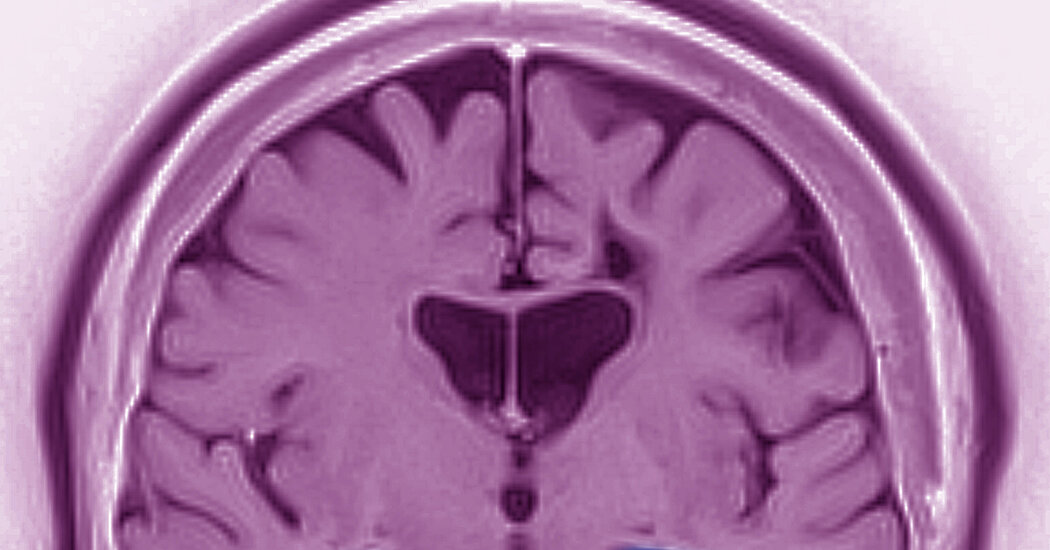

A rare but severe flu complication called acute necrotizing encephalopathy (ANE) is increasing among children, with recent cases rising during the past flu seasons. ANE causes rapid brain swelling, seizures, and can be fatal or lead to long-term disabilities. Most affected children are around age 5, and the condition often progresses quickly from mild flu symptoms to neurological emergencies. Experts emphasize the importance of flu vaccination, especially as vaccination rates are currently low, to prevent such severe complications. Early recognition of symptoms is crucial for timely treatment.